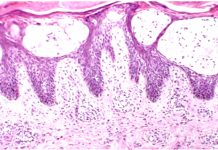

Bazal hücreli karsinom insanda en sık görülen kanserdir. Bazal hücreli karsinom yavaş büyür ve çok nadiren metastaz yapar. SCC gibi immünsüpreselerde ve DNA tamir bozukluklarında sık görülür. Hedgehog yolağındaki PTCH1 geninde bozukluk vardır. Gorlin sendromunda familyal olarak çok sayıda BCC görülür. Histolojik olarak bazal hücreler periferde palizadik dizilime sahiptir. Tümör adaları çevre stromadan çekilmeler gösterir (trikoepitelyoma ile ayrımda önemli) klinikte inci benzeri papüller ve telenjiektatik görünüm vardır.. Pigmente formları malign melanomla karışır.. Rodent ülser tipiktir. Güneşe maruz kalan yerlerde daha sıktır. Squamöz hücreli karsinomun aksine HPV ile ilişkili değildir. Bazal hücreli nevüs sendromunda herediter bazal hücreli karsinom, erken yaşta ve çok sayıda ortaya çıkar. Kemik anomalileri, sinir, göz ve üreme sisteminde anomaliler vardır. (Cevap D)